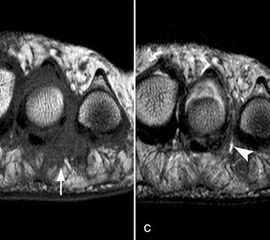

Zwischen der plantaren Platte und der Grundphalanx ist in der Mittellinie des Gelenkes ein kleiner Rezessus vorhanden (Abb. 9).

Dieser flüssigkeitsgefüllte Raum darf nicht als Ruptur der plantaren Platte fehlinterpretiert werden 23. Verletzungen der plantaren Platte erfassen immer auch den medialen oder lateralen Zügel.